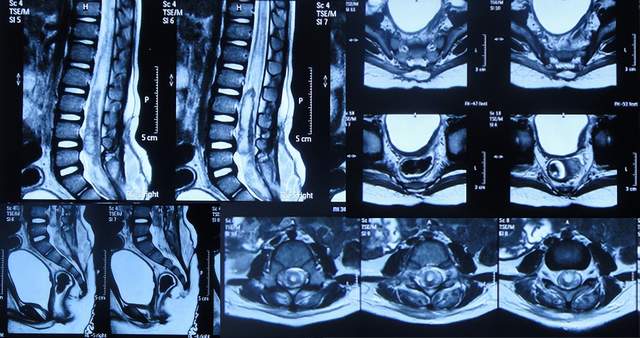

住院治疗18天即2022年7月18日,查头颅CT示脑室有缩小(图-12)。

图-12:2022年7月18日头颅CT

住院治疗63天即2022年9月1日,常规查头颅CT示脑室引流术后状态(图-15)。

图-15:2022年9月1日头颅CT

2022年10月12日(住院治疗104天),已夹闭脑室引流管3天,查头颅CT示脑室未见异常(图-17)。

图-17:2022年10月12日头颅CT

2022年10月19日(住院治疗111天),拔除了脑室引流术,拔管前和拔管后头颅CT(图-18)对比。

图-18:2022年10月19日拔管前后头颅CT对比

2022年10月25日(李小勇脑脊液科治疗117天),出院时:精神状态挺好,大小便正常,虽右腿走路稍差但走路速度变快,变稳(图-19);出院时头颅CT示未见异常(图-20)。

图-20:出院时头颅CT